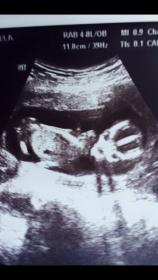

Do u think it is the leg??? I can clearly see it but ur making me doubt now lol

This is my daughter same gestational age & i dont see the pointy nub & i can see the girly nub .. some would told me there was no nub but i can see it too & it was confrim tru blood that she is a female :)